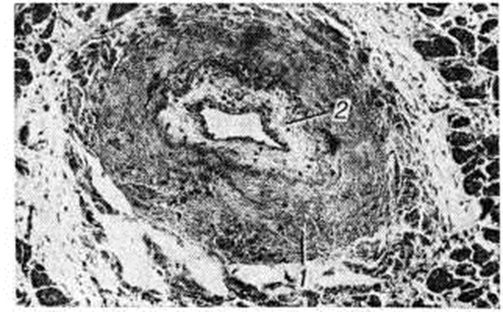

В заключительной стадии поражены обширные участки миокарда обоих желудочков, особенно — левого. В основном выявляются дистрофические и некротические изменения миокардиоцитов, начиная от вакуолизации перинуклеарной зоны цитоплазмы (смотри полный свод знаний Вакуолизация) и до цитолиза (рисунок 2) с полным растворением тел клеток (смотри полный свод знаний Цитолиз). От клеток остаются только следы в виде мелких зёрен липофусцина. В результате образуются ареактивные участки депаренхимизации миокарда (рисунок 3) с так называемой пустой сеткой, в дальнейшем замещаемые соединительной тканью. Ряд мышечных волокон подвергается мелкоглыбчатому и мелкозернистому распаду с образованием фуксинофильного детрита, резорбция которого также заканчивается миофиброзом. Процесс вакуолизации и лизиса распространяется и на клетки эндотелия кровеносных сосудов в очагах поражения. Процесс в целом напоминает дистрофический (деструктивный) миокардит. Нередко обнаруживаются также воспалительные лимфогистиоцитарные инфильтраты с примесью сегментоядерных лейкоцитов; в сочетании с дистрофическими изменениями создаётся картина смешанной формы идиопатического (аллергического) миокардита. Внутриорганные мелкие артерии и артериолы изменяются по типу аллергического васкулита (смотри полный свод знаний) — от фибриноидного некроза стенки (рисунок 4) до облитерирующего панваскулита. Все эти процессы обнаруживаются на фоне распространённых полей кардиосклероза различной зрелости (рисунок 5), подобно миокардитическому кардиосклерозу (смотри полный свод знаний Кардиосклероз), что свидетельствует о прогрессирующем и длительном течении поражения миокарда. В дистрофический и рубцовый процессы вовлечены и различные отделы проводящей системы с миоцитолизом (рисунок 6).

Рис. 3. | ||